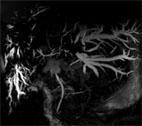

Figure 1: Arterial phase 3-D VIBE FS, PAT 2, 25 second breath-hold, 3 mm, 180 x 320 matrix, 25 x 34 cm

Evaluation of the liver demonstrates several ill-defined infiltrative masses which demonstrate progressive peripheral enhancement on delayed phase sequences with lack of central enhancement (see Figure 1).